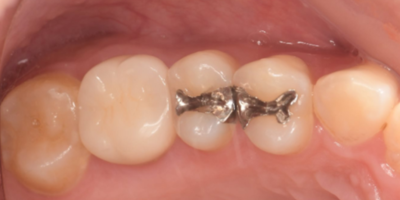

初診時口腔内写真

初診時パノラマX線写真と口腔内写真。

右上6に腫脹と排膿がみられた。